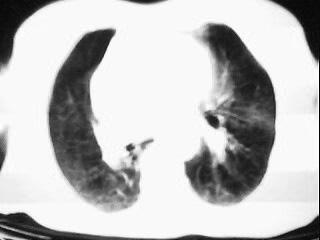

女,79,咳 嗽月余,无其它不适

1)两肺炎症。2)食管裂孔疝可能;建议行上消化道钡餐检查。

后纵隔内左心房至肝左叶后方椎体中线偏左巨大软组织包块,其壁均匀比较薄,其内可见宽气液平。

考虑食管裂孔疝。建议钡餐检查